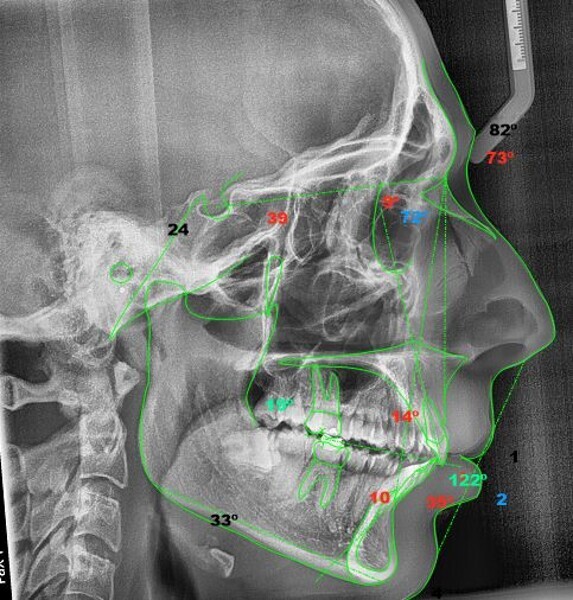

In the radiographic analysis, the dental panoramic tomogram revealed that the two mandibular third molars were unerupted and horizontalised in the mandible. Nothing else relevant was observed in the radiograph (Fig. 3). A cephalometric radiograph was used to perform the cephalometric analysis according to Steiner,6 Ricketts7, 8 and McNamara9 (NemoCeph Studio, Nemotec Fig. 4).

In the Steiner analysis, the SNB angle of 74° suggested mandibular retrusion. Likewise, the ANB angle of 7° indicated Class II, which was also confirmed by Wits analysis (8.3 mm). The results indicated a protrusion of the maxillary incisors and a decreased inter-incisal angle of 118°, which suggested protrusion of the maxillary and mandibular incisors (Fig. 5).

In the Ricketts analysis, a dolichofacial pattern, that is, a facial axis of 84°, was diagnosed. The analysis also confirmed the protrusion of the incisors (Fig. 6).

The McNamara analysis revealed that the size of the mandible that would correspond to the dimensions of the maxilla (91.0 mm) would be between 114.0 mm and 117.0 mm and not the current size of 111.9 mm,9 indicating that the mandible was smaller than it should have been. However, the maxillomandibular difference was 20.9 mm, indicating a Class II skeletal pattern (Fig. 7). From the aforementioned information, we determined a Class II skeletal pattern and dental relationship with retrusion of the lower jaw and an increased overjet and overbite.